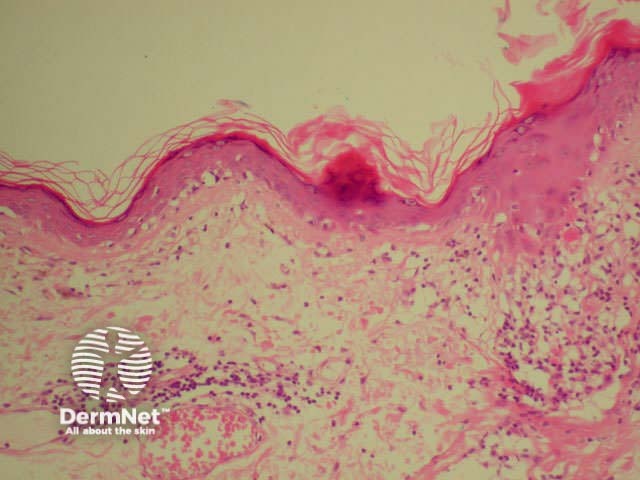

Dermatopathological findings in SLE include a lichenoid tissue reaction and a band of immunoglobulins at the dermo-epidermal junction (detected by direct immunofluorescence of clinically involved skin).

Dermatopathology of systemic lupus erythematosus This shows a dense perivascular and periadnexal lymphocytic inflammatory infiltrate and interface changes with vacuolar degeneration of basal layer

Medium-powered view